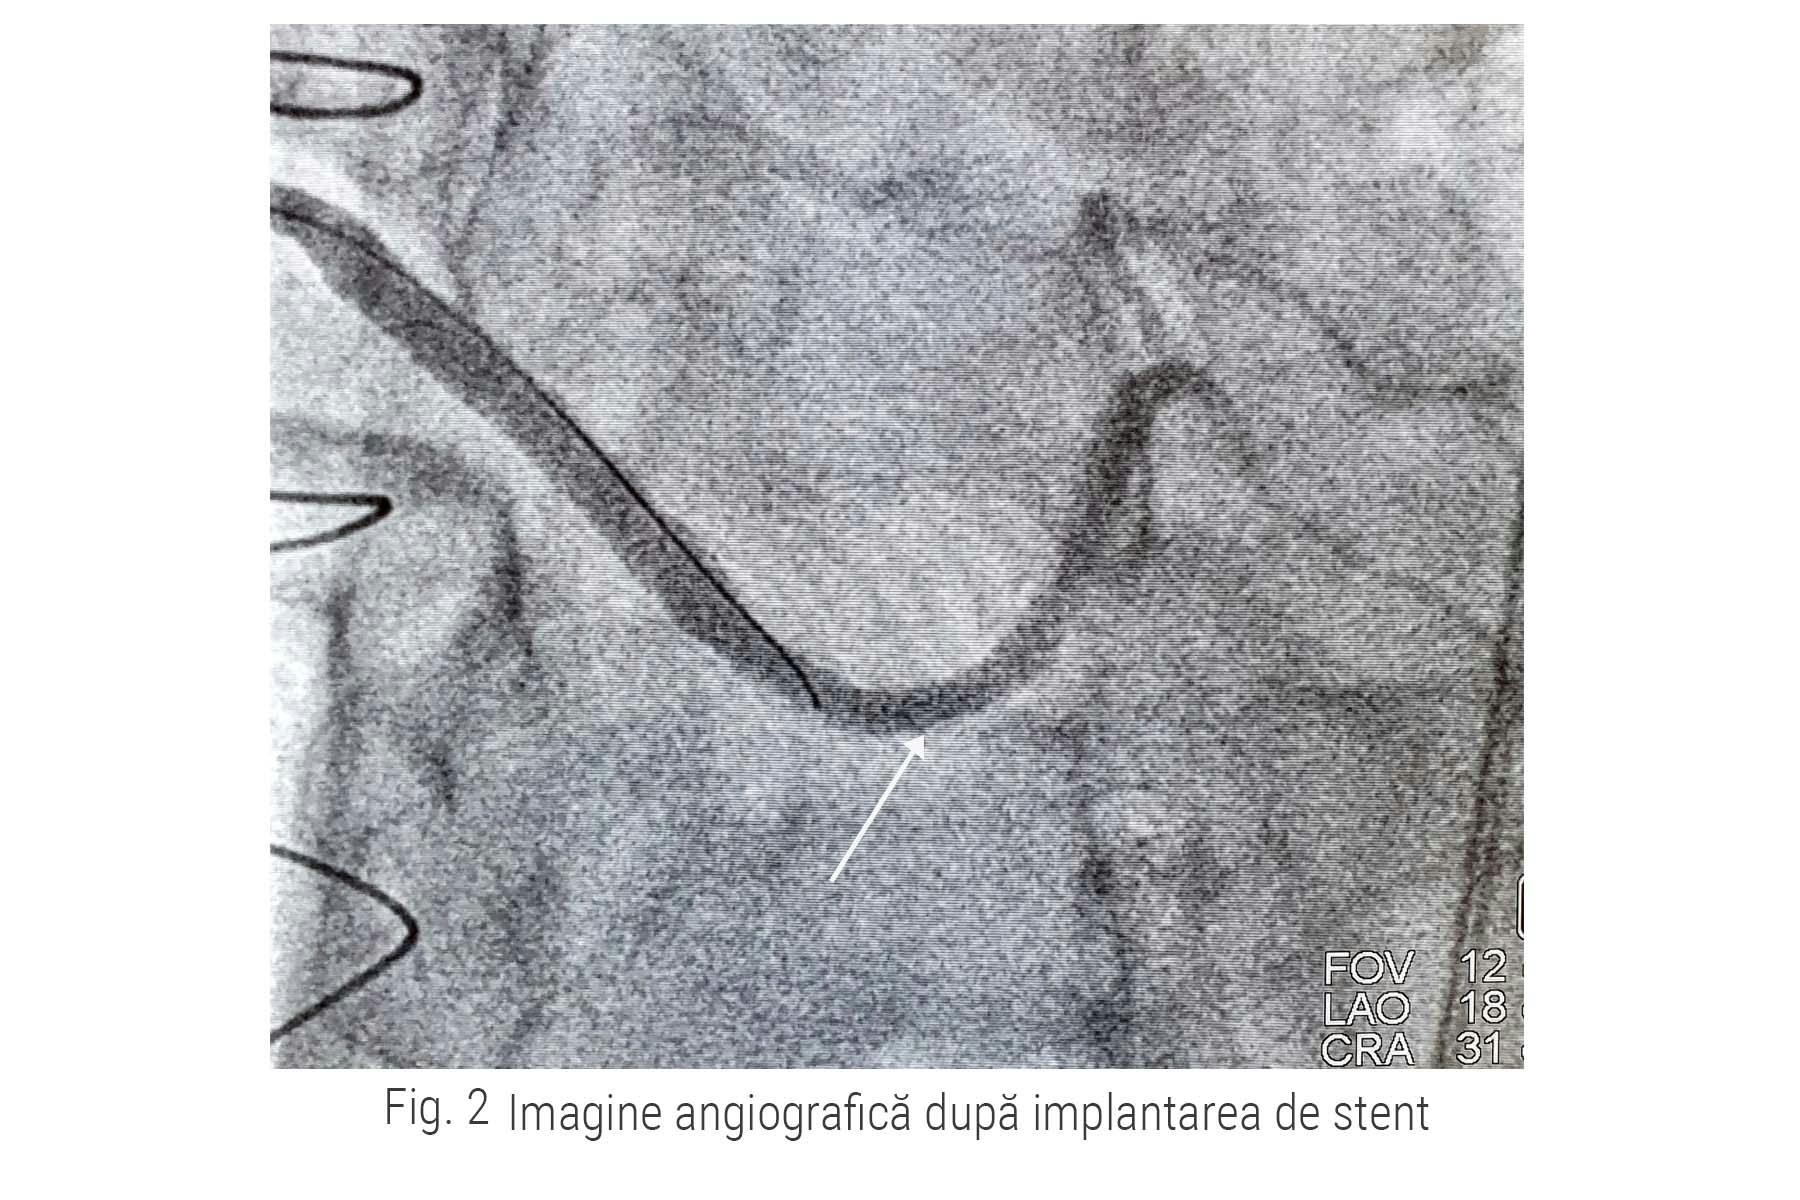

În cazul pacientului nostru, angioplastia cu stent intra-bypass a avut un rezultat excelent, fluxul sanguin la nivelul vasului afectat fiind reluat complet până în distalitate, așa cum se poate observa și în imaginea de mai jos. (fig. 2)